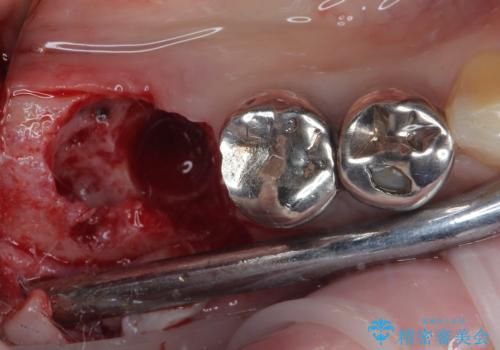

- 「歯を抜いたので、インプラントを入れてほしい」という主訴で来院された患者様です。

他院で歯根破折により抜歯をしたとのことでした。

CTにより残存骨量を確認しインプラント埋入を行っていくこととしました。